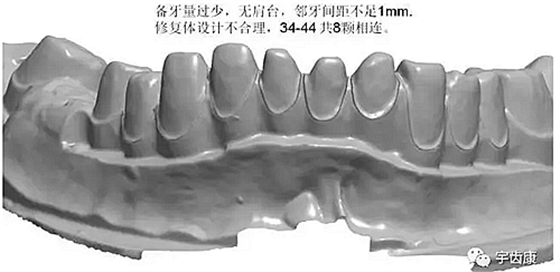

1、臨床備牙不合理或基牙條件不適合做氧化鋯

如:無肩臺(tái)、凹面肩臺(tái)、邊緣線不清晰、雙重邊緣線、備牙空間不足、基牙有倒凹或牙橋沒有共同就位道、基牙切端或頜緣過于尖銳等等。